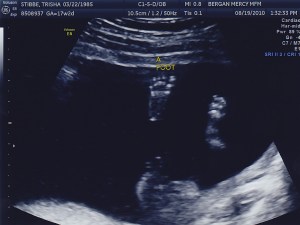

Today was the BIG appointment!!! They were able to confirm that the babies are identical. Yay!